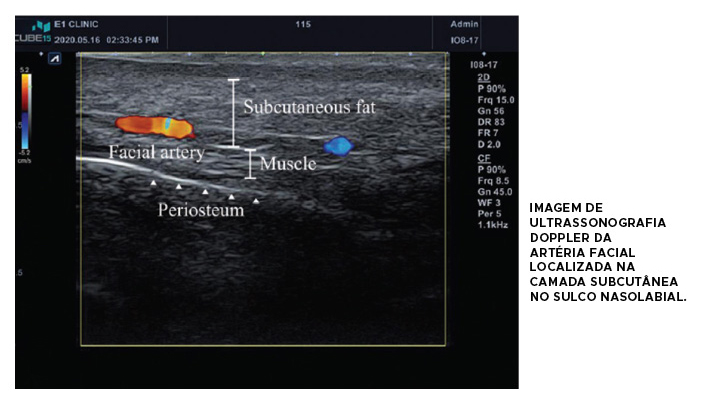

Pensando no preenchimento do sulco nasolabial, temos que lembrar que esta é uma área de grande mobilidade e que a artéria facial está passando nesta região, tornando-se mais superficial a medida que se aproxima da fossa piriforme, onde vira a artéria angular.

Sendo assim, é mais seguro utilizarmos cânula para este procedimento, utilizando preenchedores de G’ médio/moderado, com boa viscoelasticidade e coesividade e preferencialmente com partículas menores. Este deve ser injetado no plano subcutâneo mais superficial por retroinjeção.